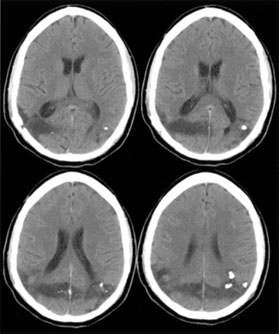

Among adults with infarction, blindness is permanent in 25%57 and residual visual field defects are common in the rest. Bioccipital CT lucencies carry a poor prognosis for recovery, but abnormal visual evoked potentials do not correlate with severity or outcome.60 Although the abnormalities on visual evoked potentials are not diagnostic, they tend to improve as vision returns.75–77 Transient cerebral blindness can last hours to days, often with full recovery (Table 2). Both ictal and post-ictal cerebral blindness are reported in children and adults.78–80 Transient cerebral blindness can occur with metabolic insults,81–83 hypertensive encephalopathy,84 hydrocephalus,85 trauma,72,86 and cortical venous thrombosis.87 Toxins are an important cause, especially chemotherapeutic agents.88–92 Cerebral blindness is associated with the iodinated contrast agents used in angiography:60,93,94 CT scans with contrast show disruption of the blood–brain barrier in the occipital lobes93,94 as early as 1 hour after angiography.95 TABLE 2. Causes of Transient Cerebral Blindness

The pathogenesis of transient cerebral blindness varies with the cause. Vasospasm is blamed in head trauma,96 eclampsia,97,98 methamphetamine abuse,99 and meningitis, which also may induce vasculitis.77,100 Circumstantial evidence for vasospasm includes a correlation of traumatic cerebral blindness with prior migraine.86 Angiographic contrast agents may cause breakdown of the blood–brain barrier under osmolar stress and subsequent neurotoxic effects,95 providing a rationale for dexamethasone and mannitol as specific therapy in this context. Pediatric cerebral blindness is not uncommon. Children may not complain of visual loss but present with agitation, disorientation, and unsteadiness.73,96,101 During tests of vision they may not respond or may confabulate answers.101,102 Further observation shows that they do not fix, follow, or make saccades to objects, blink to threat, or show optokinetic responses.70,73,102 There can be an associated strabismus. Major causes include head trauma, bacterial meningitis,76,77,100,102 and hypoxia from cardiac or respiratory arrest.102 Other causes include encephalitis, as well as metabolic83,102,103 and toxic99 conditions (Table 3). Seizures are common, and mental retardation is a frequent complication in children with cerebral blindness after meningitis. TABLE 3. Causes of Pediatric Cerebral Blindness